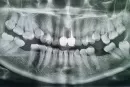

Прикрепленые фото

Да, судя по ортопантомограмме, восьмые зубы подлежит удалению, так как для их полного прорезывания в зубном ряду места недостаточно. На данный момент можно стараться тщательно вычищать, чтоб не возникло воспаление слизистой, проводить антисептическую обработку полости рта Мирамистином или Хлоргексидином. После самоизоляции обратиться к стоматологу-хирургу.